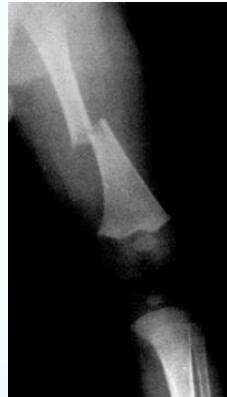

- Femur shaft fracture

- <1 year of age (70%)

- Transverse fracture

- Humeral shaft fracture

- <3 years of age